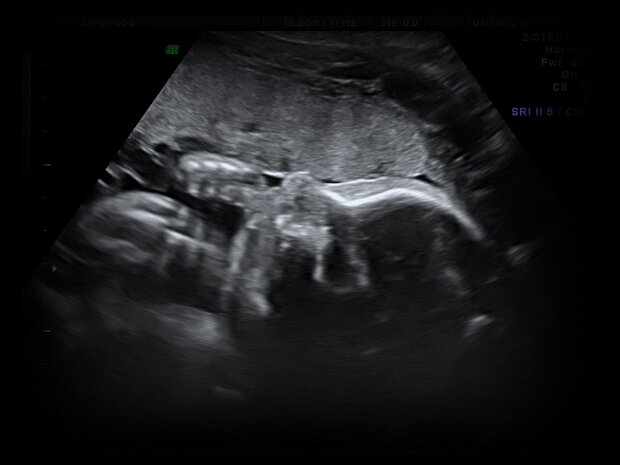

Sebastian's Sonograms